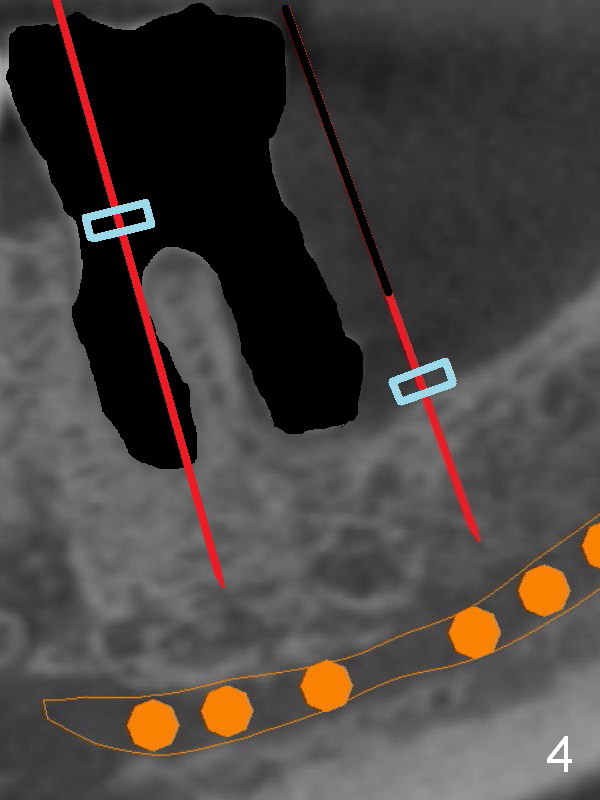

There is severe bone resorption around the distal root of the lower left 1st molar of the 56-year-old man (WG), while the loss of the 2nd molar is associated with limited bone height (Fig.1). A 5x14 mm implant will be placed at the mesial socket of #19 and 5.9 or 6.4x6 mm one is at the mesial site of #18 (Fig.7-9). Use a 2 mm pilot drill with 6 mm stopper from Sinus Master Kit (with extension) to initiate osteotomy at #18 immediately distal to the crown of #19, parallel to the long axis of the latter (Fig.2). After inserting a parallel pin at #18, extract the tooth #19 (Fig.3, antibiotic pending) and start osteotomy with a 2 mm pilot drill with 14 mm stopper (Fig.4). Insert the calibrated parallel pin at #19 (Fig.5) and measure the distance between the two parallel pins (approximately 10 mm, Fig.7). Sequential osteotomy and application of the Tatum taps (Fig.6 red rectangle) will push the septum distal (green arrow). As to #18 osteotomy, trephine, final and tap drills are to be used with control of the depth: 6 mm (Fig.7,9).